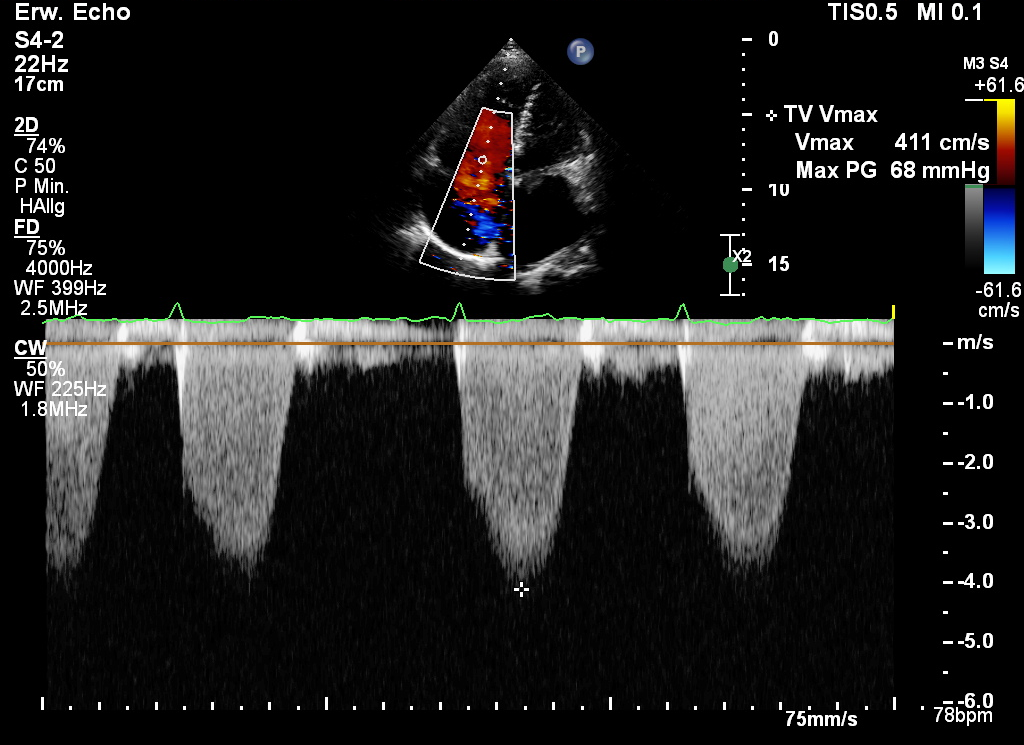

cW-Doppler